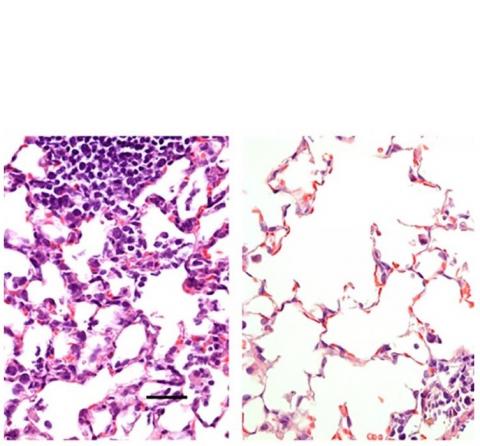

Les chercheurs de l'Université de Washington à Saint-Louis ont mis au point un vaccin anti-COVID-19 délivré par le nez et qui protège les souris du virus. L'administration nasale (tissu pulmonaire de droite sur visuel) produit une réponse immunitaire plus étendue que l'injection intramusculaire (tissu pulmonaire de gauche). Prochaine étape, tester le candidat sur des primates non humains puis chez l’Homme, pour valider sa sécurité et son efficacité.

Tissu pulmonaire : vaccination par injection intra-musculaire à gauche et par voie nasale à droite (Visuel Hassan et al.)

Les chercheurs qui ont comparé les 2 modes d’administration (injection intra-musculaire et administration nasale) chez la souris, constatent que la voie d'administration nasale a empêché l'infection dans les voies respiratoires supérieures et inférieures - le nez et les poumons - suggérant que les personnes vaccinées ne propageraient pas le virus et ne développeraient pas d'infection.